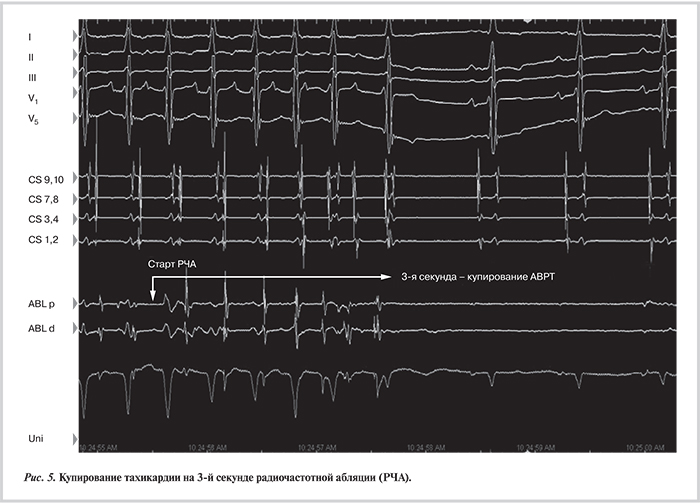

Под рентгенологическим и эхокардиографическим контролем (внутрисердечная ЭхоКГ) выполнена пункция межпредсердной перегородки. Абляционный электрод проведен в полость левого предсердия, выполнена его анатомическая 3D-реконструкция. В области латеральных отделов фиброзного кольца митрального клапана на фоне клинической АВРТ верифицированы участок регистрации потенциала ДАВС и ранняя ретроградная предсердная активация (рис. 4, см. цв. вклейку). В этой области было нанесено РЧ-воздействие (45 °C, 40 Вт, суммарной длительностью 90 с, ирригация 17 мл/мин), на фоне которого отмечалось купирование АВРТ на 3-й секунде воздействия (рис. 5). В ходе контрольного эндокардиального ЭФИ в течение 30 мин при желудочковой стимуляции сохранялась ВА-диссоциация. При программированной стимуляции предсердий [эффективный рефрактерный период АВ-соединения 500·260 мс, точка Венкебаха 315 мс, время восстановления функции синусного узла (ВВФСУ) 1120 мс, корригированное ВВФСУ 520 мс] АВРТ не рецидивировала. Пациент был выписан из стационара на 2-е сутки после операции в удовлетворительном состоянии без антиаритмической терапии.